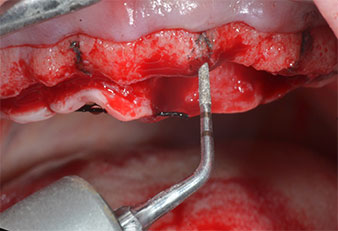

A flame-shaped, diamond-coated piezoelectric instrument (Piezomed I1) was used to mark the implant positions and to perform pilot preparation (Fig. 3). Care was taken to use an up and down movement, with reduced power, full irrigation and low pressure (below 300 g). Next a pilot instrument (Piezomed I2A/I2P) was applied for the initial 2 mm diameter enlargement of the implant sites (Fig. 4), followed by a 3 mm insert (Fig. 5).

Ultrasonic marker instrument Piezomed

Fig. 3: Preparation with the ultrasonic marker instrument Piezomed I1 is performed in an up and down movement, parallel to the long axis of the working part.